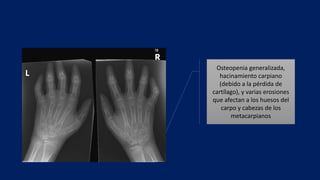

Osteopenia generalizada,

hacinamiento carpiano

(debido a la pérdida de

cartílago), y varias erosiones

que afectan a los huesos del

carpo y cabezas de los

metacarpianos